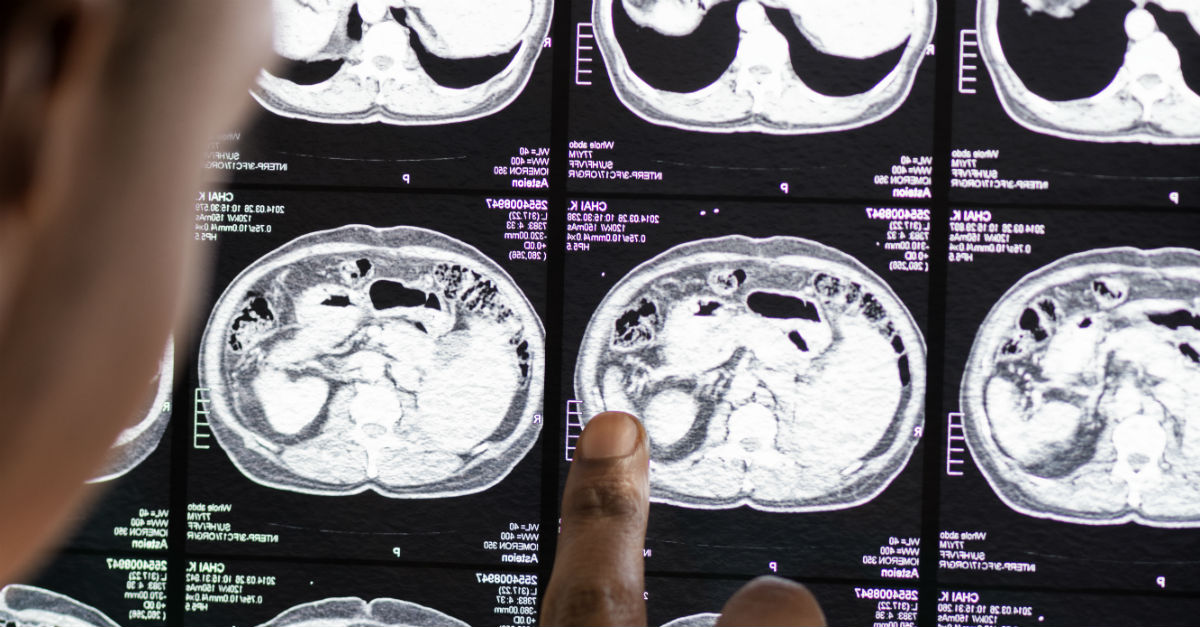

La joven mujer llevaba dentro de ella un gemelo parásito, que inicialmente fue confundido con un tumor común. No obstante, algunas cosas en el examen desconcertaron a los médicos, ya que había estructuras que se parecían a vértebras, costillas y otros huesos. Todo esto se debió a la concentración de calcio en estos lugares, que fueron más evidentes en el examen de imágenes.

El personal médico decidió que sería interesante extirpar el tumor y analizar de qué se trataba, ya que sospechaba de la rara condición. Por lo tanto, al quitar la piedra de 36 centímetros de alto, 16 de ancho y 10 de profundidad, tuvieron una visión terrible. Era una maraña de cabello, huesos y piel. Además, fue el mayor gemelo parásito encontrado en la historia.